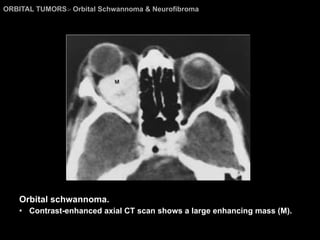

Orbital Schwannoma & Neurofibroma On CT and MR imaging, orbital schwannomas appear as  sharply marginated , oval or fusiform, intraconal or  extraconal masses Moderate to marked enhancement.  The optic nerve is always displaced and may be engulfed by the tumor.

ORBITAL TUMORS >  Orbital Schwannoma & Neurofibroma Orbital schwannoma. Contrast-enhanced axial CT scan shows a large enhancing mass (M).